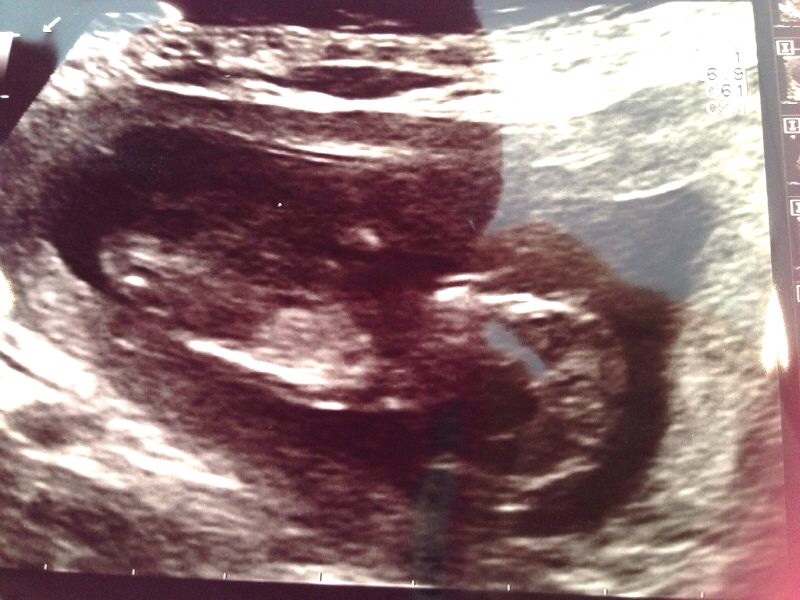

Other pics are of DD2!

It's another girl!!! JEEEEEEJJ!!!!

Confirmed at 15 weeks and 16 weeks and 18 weeks!